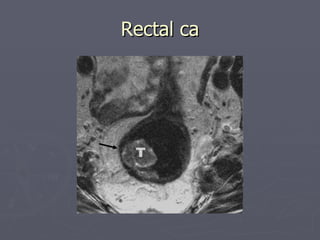

Rectal ca

Abdominal MRI Problemsolving tool in liver, pancreatic, renal and adrenal lesions Primary modality in local staging of rectal ca, endometrial ca, cervical ca, prostate ca, vaginal ca Non-invasive modality in evaluating pancreaticobiliary tract – MRCP Scrotal and penile imaging Uterus and ovary imaging

• 76.